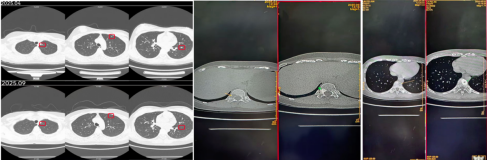

2025-09复查CT提示肺部转移灶明显缩小,原右肺的微小结节也几乎消失;骨转移灶原来溶骨的部位出现成骨,考虑好转。治疗前后影像学检查对比如下。